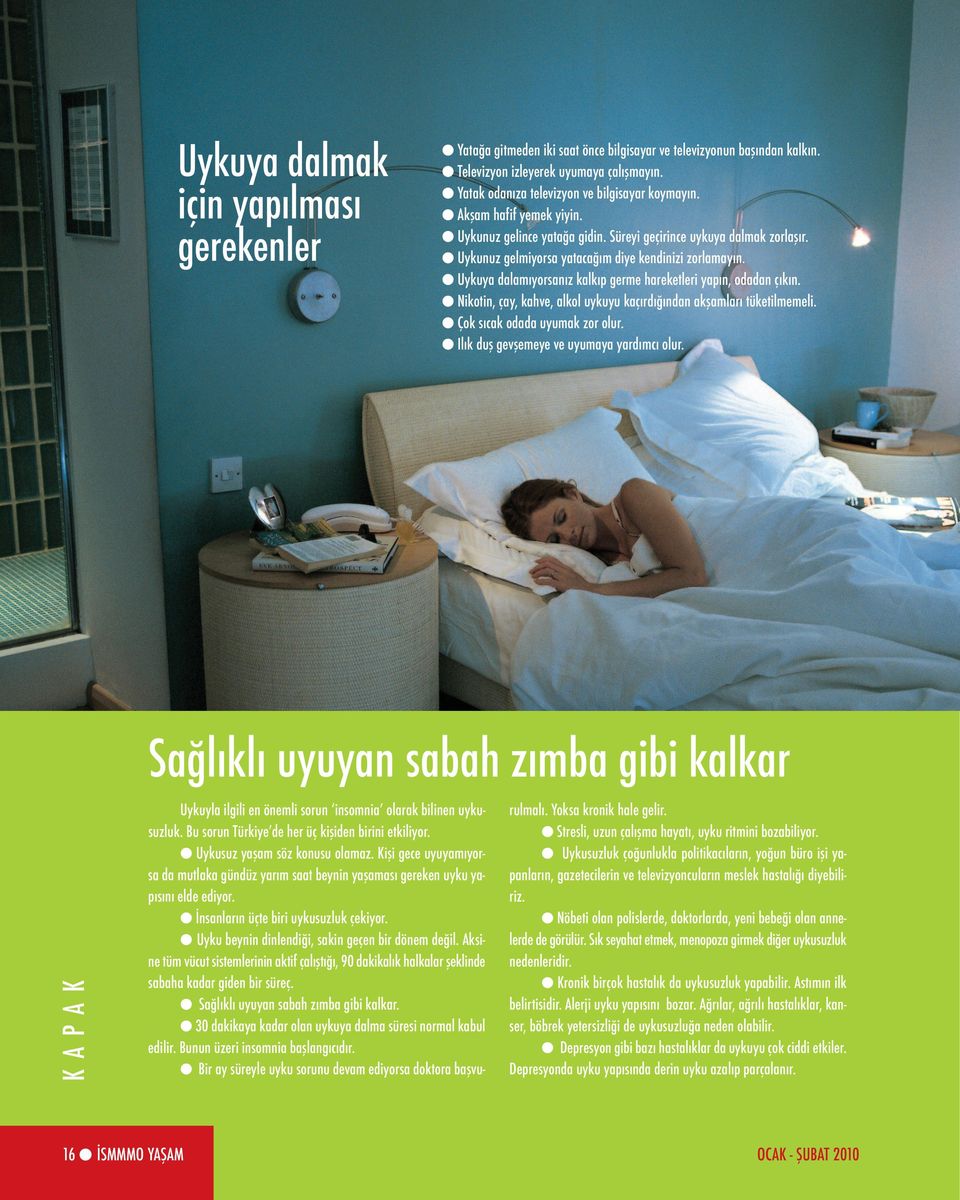

Koridorundaki resimleri alıp yeni binanın koridoruna asıyorlar. Buraya yazılanların hakları sir anthony hopkins e aittir. Bu da doğaldır çünkü sağlıklı olmak için iyi bir uyku gereklidir. Kişisel verilerimin bana özel ürün ve hizmetlerin önerilmesi ile tanıtılması için işlenmesini ve bu doğrultuda aşağıda belirttiğim iletişim bilgilerime reklam promosyon kampanya tanıtım ve benzeri ticari.

Bence denenebilir keza horlama gercekten ciddiye alinmayan ama bir o kadar da onemli bir saglik sorunu. İstanbul okan üniversitesi hastanesi tanıtım pazarlama süreci kişisel verilerin korunması ve i̇şlenmesi aydınlatma metni kapsamında. Uyku kalitenizin yüksek olduğundan emin olun. Site içeriği küçükler için.